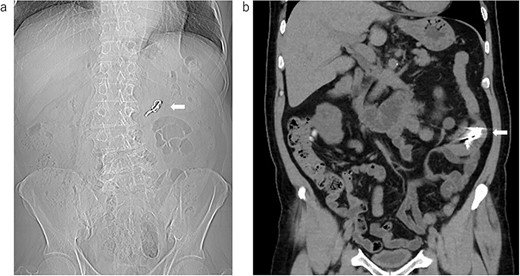

Abdominal examination findings were normal. Blood exams showed no unusual findings except slight renal dysfunction (BUN 38.2 mg/dl, Cre 1.98 mg/dl). We asked the previous doctor to provide the results of the imaging test (Fig. 1a and b). After that, we performed X-ray (Fig. 2a) and CT (Fig. 2b) examinations at our hospital and confirmed that the denture was still in the small intestine. Since it remained in the intestinal tract for a long time, there was no possibility of spontaneous excretion. Although the patient was asymptomatic, we decided to perform surgery because the patient himself wanted to have it removed.

The image data were obtained by the previous doctor; (a) X-ray examination: the arrow shows the swallowed denture; (b) the coronal image of the CT: the arrow shows the swallowed denture.